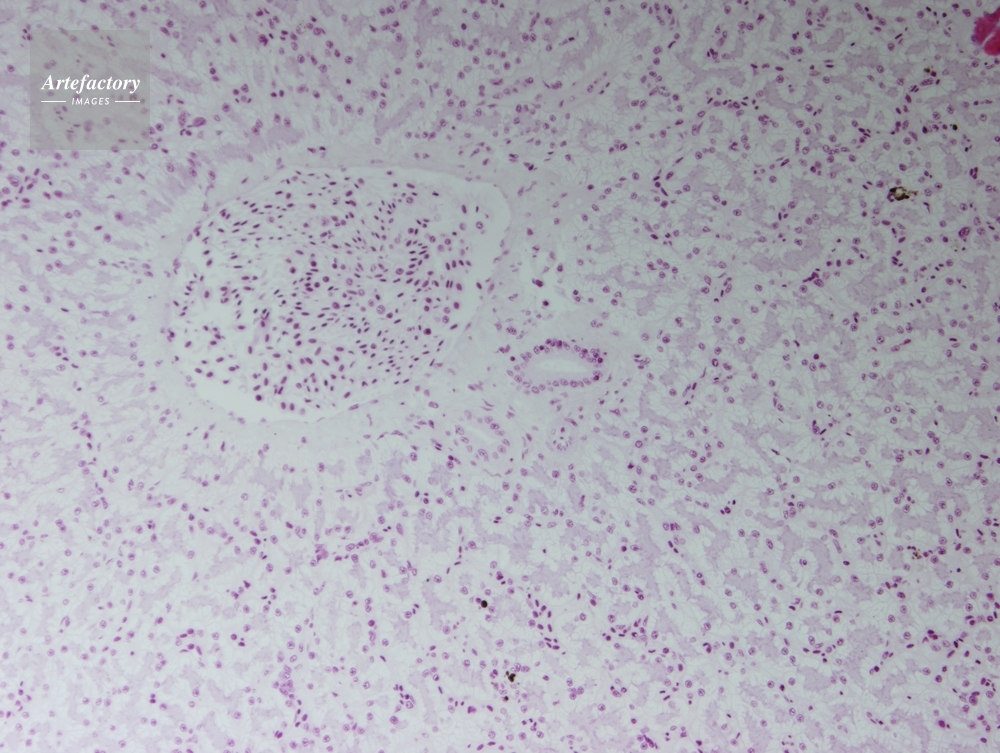

| 作品タイトル | カエル,肝臓 | モデルリリース | なし | |

| 作家 | OLYMPUS CORPORATION Technolab | プロパティリリース | なし | |